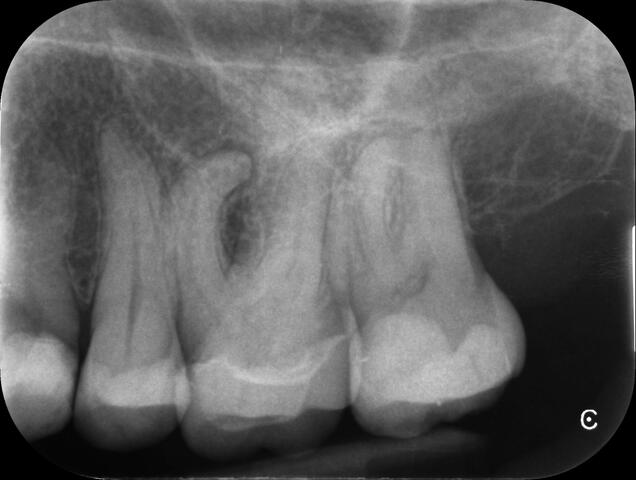

There are a number of ways to decide whether you need root canal treatment and the specific x-rays, scans and tests help diagnose your problem.An important sign is the type of pain you have been having with a tooth. It helps me decide if a tooth is in need of treatment and even if it saveable.

I really enjoy undertaking root canal treatments - rising to the challenge and helping people out of dental pain for the long term.I was privileged to be asked to speak at the 2016 BDA Conference, where I have a lecture about providing quality endodontic outcomes to patients, working as a generalist. Avoiding problems and pitfalls and maximising efficiency. One of the main matters that he covered was understanding that what is seen on plane radiography is utterly misleading and should not be the criteria by which a generalist continues treatment once it has been started.

At the 2016 BDA Conference, Thomas spoke about providing quality endodontic outcomes to patients, working as a generalist. Avoiding problems and pitfalls and maximising efficiency. One of the main matters that he covered was understanding that what is seen on plane radiography is utterly misleading and should not be the criteria by which a generalist continues treatment once it has been

started.